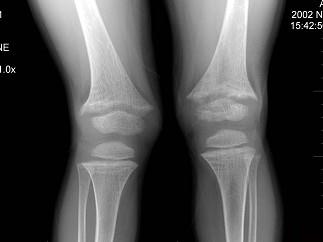

问题 男,6岁,睡眠差,夜惊,多汗;出牙较迟;血清磷减低、血清钙减低、碱性磷酸酶升高卜,请结合图像选择最佳选项 ( )

选项 A、肾性维生素D缺乏病 B、脆骨病 C、骨软化症 D、先天性骨梅毒 E、维生素D缺乏病

答案 E